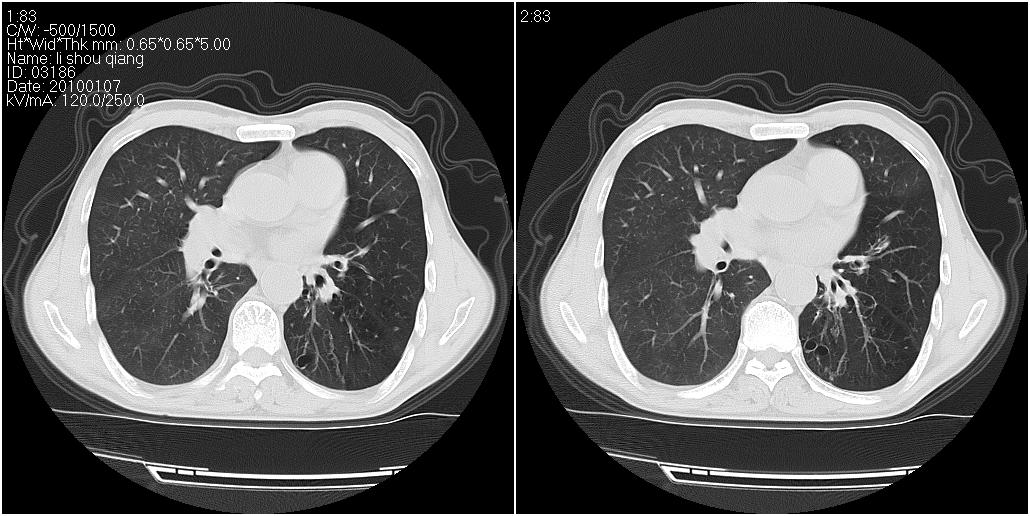

右肺中叶外侧段见一不规则的软组织肿块,边缘可见毛刺,并见厚壁空洞,与胸膜分界欠清。另左下肺见多个小囊状扩张区

右肺中叶外侧段可见团块影,外形不规则,内见空泡征。左下肺见蜂窝状低密度透亮影,部分层面主动脉旁瘤样突出。考虑右肺中叶外围型肺癌可能性大,左下肺支气管扩张,主动脉弓瘤样突出。

1)考虑右肺中叶周围型肺癌并癌性空洞形成。2)左肺下叶支气管扩张可能性大。

支持1)考虑右肺中叶周围型肺癌并癌性空洞形成。2)左肺下叶支气管扩张可能性大。